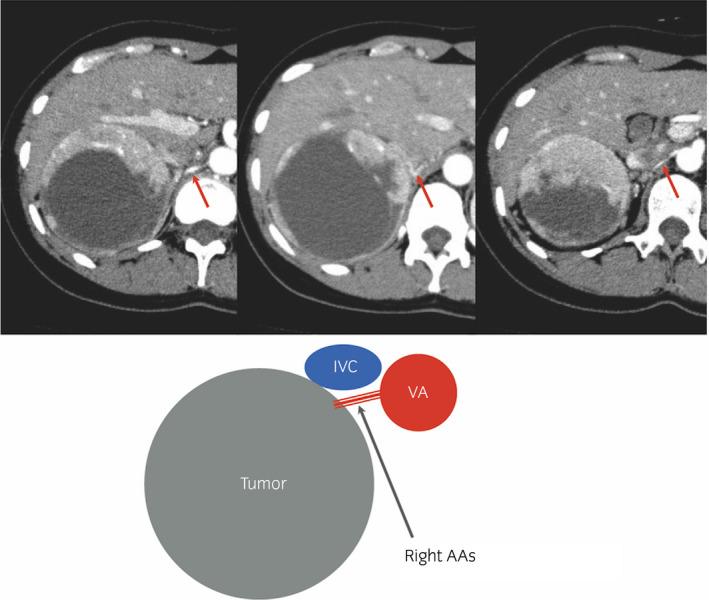

We present three patients with right adrenal pheochromocytoma over 10 cm diameter: a 40-year-old woman, 63-year-old man, and 66-year-old woman. They were diagnosed by 123I-MIBG scintigraphy and received preoperative antihypertensive treatment with 16 mg/day of doxazosin. Open adrenalectomy was performed with early right adrenal artery ligation between the inferior vena cava and ventral aorta (Step 1) as well as between the tumor and upper pole of the right kidney (Step 2). There was no severe intraoperative hypertension, and no recurrence was observed over 33 months, postoperatively.

我们报告了3例直径超过10厘米的右肾上腺嗜铬细胞瘤患者:一名40岁女性、一名63岁男性和一名66岁女性。他们通过123I-MIBG闪烁显像确诊,并接受了每日16毫克多沙唑嗪的术前降压治疗。采用开放肾上腺切除术,早期在腔静脉和腹主动脉之间结扎右肾上腺动脉(步骤1)以及在肿瘤和右肾上极之间结扎(步骤2)。术中未出现严重高血压,术后33个月未观察到复发。